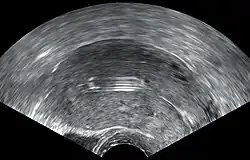

- Una "espiral perdida" ocurre cuando el hilo no puede ser sentido por una mujer en la revisión de rutina y no se ve en el examen con espéculo. Se pueden usar varios dispositivos colectores de hilo o pinzas simples para tratar de agarrar el dispositivo a través del cuello uterino. En los casos poco frecuentes en que esto no sea posible, se puede realizar una ecografía para verificar la posición de la espiral y excluir su perforación a través de la cavidad abdominal o su expulsión previa no reconocida.